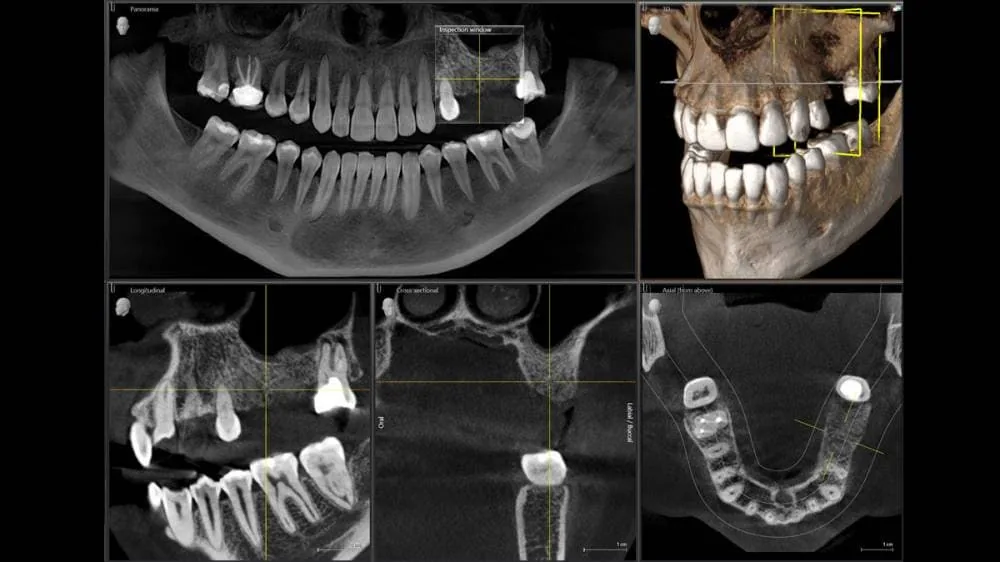

Tomografia Cone Beam

Orthophos SL 3D

A Clínica Radix oferece exames de Tomografia Computadorizada Cone Beam (CBCT) realizados com o moderno Orthophos SL 3D, equipamento de última geração da Dentsply Sirona, reconhecido mundialmente por sua excelência em diagnóstico por imagem.

Permite a obtenção de imagens tridimensionais de alta resolução das estruturas maxilofaciais, com visualização detalhada de dentes, ossos, articulações e vias anatômicas com extrema precisão.

As imagens 3D permitem mensurações exatas e análise em múltiplos planos, proporcionando maior previsibilidade nos tratamentos.

Alta definição, baixa radiação

Tecnologia avançada com protocolos de baixa dose, garantindo segurança sem comprometer a acurácia.

Tecnologia Sharp Layer

Tecnologia exclusiva que melhora a nitidez automaticamente, ajustando o foco nas camadas anatômicas de interesse.

Integração digital completa

Arquivos compatíveis com softwares de planejamento e escaneamentos intraorais para fluxos digitais.

Conforto e rapidez

Exame não invasivo, com aquisição de imagem em poucos segundos.

Aplicações clínicas

- Planejamento de implantes dentários

- Avaliação de dentes inclusos

- Análise de lesões ósseas, cistos e tumores

- Estudo das articulações temporomandibulares (ATM)

- Planejamento cirúrgico e ortodôntico

- Endodontia avançada (canais e fraturas)

Tomografia vs Radiografia

Conheça as características de cada exame e quando cada um é indicado.

Tomografia

Exame tridimensional que permite visualizar com precisão as estruturas ósseas, dentais e tecidos adjacentes em múltiplos planos.

- Visualização tridimensional completa

- Detalhamento superior de estruturas ósseas

- Ideal para implantes e cirurgias

- Avaliação de lesões complexas

Como a tomografia auxilia o tratamento

Ferramenta essencial para o planejamento e execução de diversos procedimentos odontológicos.

Cirurgias

Planejamento preciso de extrações e cirurgias bucomaxilofaciais.

Implantes

Avaliação óssea detalhada para posicionamento ideal.

Canal

Visualização precisa da anatomia radicular e lesões periapicais.

Avaliação Óssea

Análise de densidade e volume ósseo para decisões seguras.

Planejamento

Apoio visual completo para as melhores decisões de tratamento.

Qual a diferença entre tomografia e radiografia odontológica?

A tomografia computadorizada Cone Beam gera imagens tridimensionais (3D) das estruturas maxilofaciais com detalhamento superior, ideal para planejamento de implantes, cirurgias e análise de canais.

Quanto tempo dura uma tomografia odontológica Cone Beam?

A aquisição da tomografia Cone Beam dura apenas alguns segundos com nosso equipamento Orthophos SL 3D da Sirona.

O atendimento completo (acolhimento, posicionamento e exame) leva em torno de 10 a 15 minutos. É um exame rápido, não invasivo e com baixa exposição à radiação.